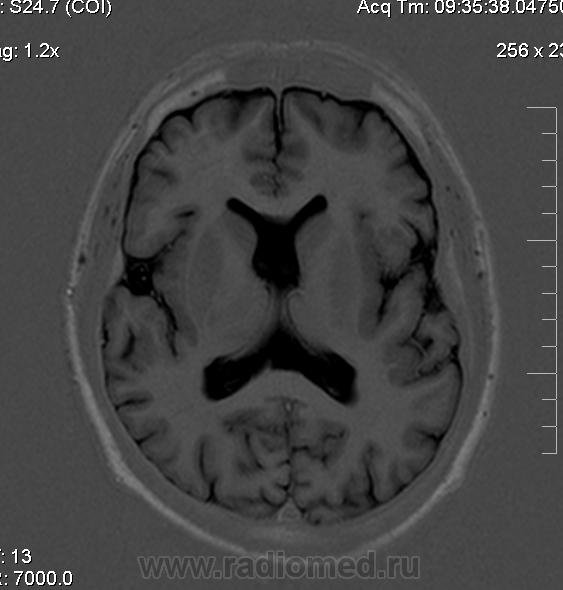

Мужчина 32 лет. Из анамнеза: перинатальное повреждение ЦНС, ДЦП, дизартрия, правосторонний верхний монопарез. С 16 лет приступы эпилепсии.

Аплазия прозрачной перегородки. Шизэнцефалия с открытыми краями в лобно-теменной области слева. Шизэнцефалия с закрытыми краями в лобной области справа? Утолщение коры по контуру расщелин и в области глазничной извилины правой лобной доли. Микрогирия? Гиперостоз костей свода черепа. Уважаемые коллеги, возможно я ошибаюсь, или есть еще аномалия?

На мой взгляд, полимикрогирия двусторонняя (конвекситальные отделы дорзальных отделов лобных долей и частично теменных, а также в базальном отделе полюса правой лобной доли) + закрытая шизенцефалия левой лобно-теменной области. Аплазия прозрачной перегородки (как признаки лобарной голопрозенцефалии).